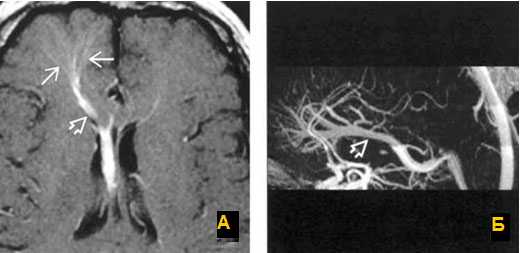

МРТ головного мозга: отмечается сочетание вазогенного (оранжевая стрелка), цитотоксического отека и кровоизлияния (зеленая стрелка). Данная МР-картина, а также расположение патологической зоны в проекции височной доли, заставляет задуматься о геморрагическом венозном НМК вследствие тромбоза вены Лаббе. Для подтверждения необходимо проведение МР-венографии или МРТ с контрастным усилением.

а) Т1 с внутривенным контрастированием. Стрелки показывают расширенные вены глубокого белого вещества, дренирующиеся в расширенную транскортикальную вену;

б) МР-венография с контрастированием показывает венозную дисплазию, дренирующуюся в расширенную внутреннюю мозговую вену. Венозная мальформация.